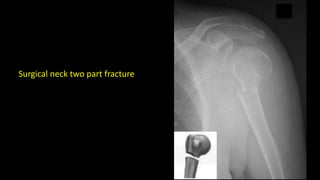

Surgical neck two part fracture

Surgical neck twopart fracture